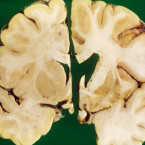

Huntingtonova choroba